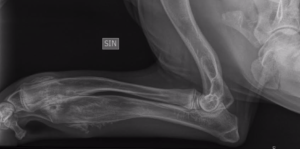

Nemin etujaloissahan on edelleen silmin nähtävät patit, ja kuten taisin viimeksi kirjoitella, mielestäni pattien ja turvotuksen laskeminen on hidastunut viime viikkoina. Turvotus ei ole tulehduksen aiheuttamaa, eikä se ole nestettäkään, kuten voisi kuvitella. Vaan: pitkien putkiluiden, eli värttinä- ja kyynärluun (sekä sääriluun) ympärille on kasvanut uudisluuta, ja se paksuntaa jalat ja saa aikaan patit!

Röntgenkuvia järkyttyneenä katsellessani sain samalla kuulla, kuinka alkuvaihe on kuumeineen, kipuineen ollut sairauden ykkösvaihetta, akuuttia vaihetta. Jonkun mahdollisen teorian mukaan koiran keho lähtee tuottamaan tuota uudisluuta jonkinlaisena reaktiona rajuna velloneen akuutin vaiheen oireille. Siitä päästäänkin siirtymään sairauden toiseen vaiheeseen, jossa nyt tätä uudisluuainesta sulatellaan ajan kanssa. Ja aikaa pattien sulatteluun on niin kauan, kuin koiran luusto vielä kasvaa ja kehittyy. Suurimmalla osalla koirista luun uudismuodostuma pitäisi sulaa pois, mutta on kuulemma tapauksia, jossa luu ei ole sulanut – ainakaan kokonaan. Lopputuloksen meille näyttää nyt vain aika.

Ja tältähän se nyt sitten näyttää: